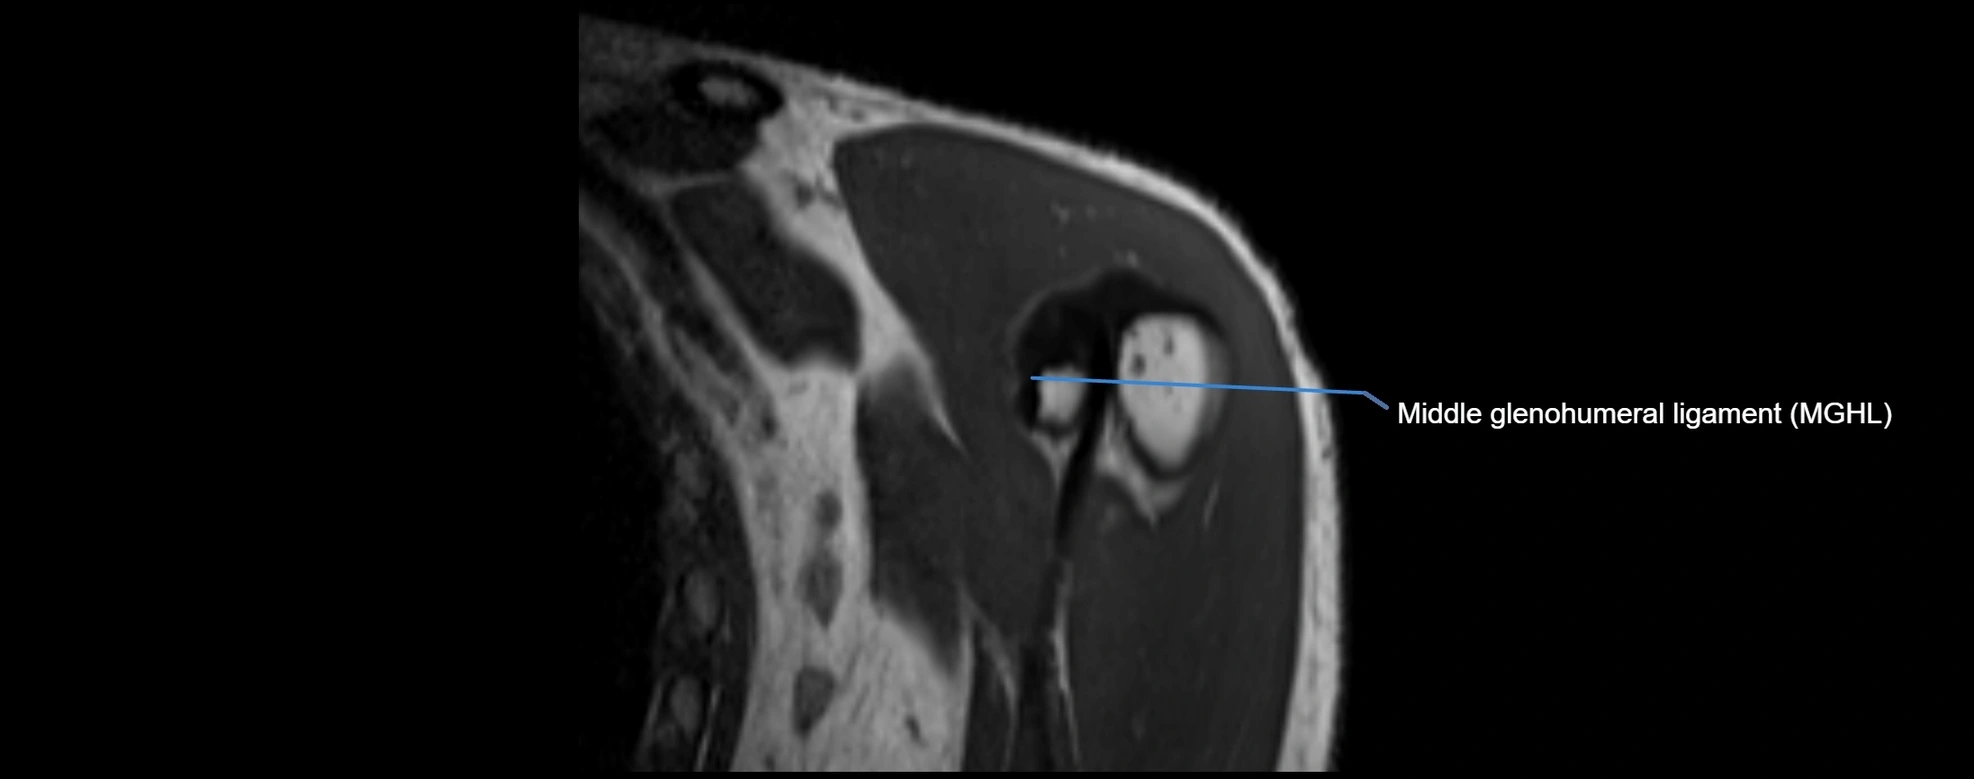

MRI Appearance

• T1-weighted images:

• Normal ligament: Low signal (dark linear band) spanning acromion to clavicle.

• Surrounding fat planes: Bright, delineating the ligament clearly.

• Marrow of clavicle and acromion: Bright due to fatty content.

• Tears: Discontinuity or irregular thickening with intermediate-to-bright signal.

• Chronic injury: Thinning, fraying, or irregular low-signal fibers with adjacent scarring.

• T2-weighted images:

• Normal ligament: Low signal, homogeneous.

• Partial tear or sprain: Focal hyperintensity or thickening.

• Complete tear: Discontinuity with fluid-bright gap between clavicle and acromion.

• Associated edema: Bright signal in distal clavicle or acromion marrow.

MRI images

image